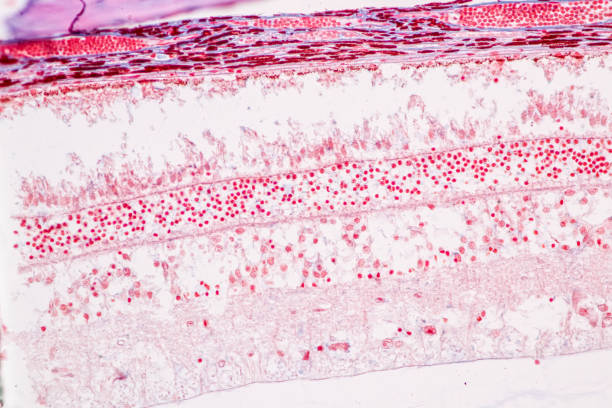

대표적으로 녹내장의 원인은 안압상승으로 인해 시신경이 손상원인이 녹내장 질환을 발생하게 합니다. 나이가 들면 노화가 진행됨으로써 눈의 각 부분 조절능력이 떨어져 안구 내의 안압이 높아지면서 이로 인해 뇌로 연결되는 시신경이 손상되면서 녹내장이 발생됩니다. 녹내장이 나타나면 시야가 좁아지면서 심하면 실명할수도 있습니다. 녹내장을 유발하는 대표적인 원인에 대해 알아보겠습니다.

녹내장 원인 두 번째는 고도 근시입니다. 고도 근시는 안구의 길이가 상대적으로 길어진다고 알려져 있습니다. 안구의 길이가 길어질수록 안구와 연결되는 시신경을 지지하는 구조가 얇아지고 힘을 덜 받게 되는데 이로 인하여 구조가 약해지면서 안압이 점차 시신경으로 전달되어 녹내장을 유발할 수 있습니다.